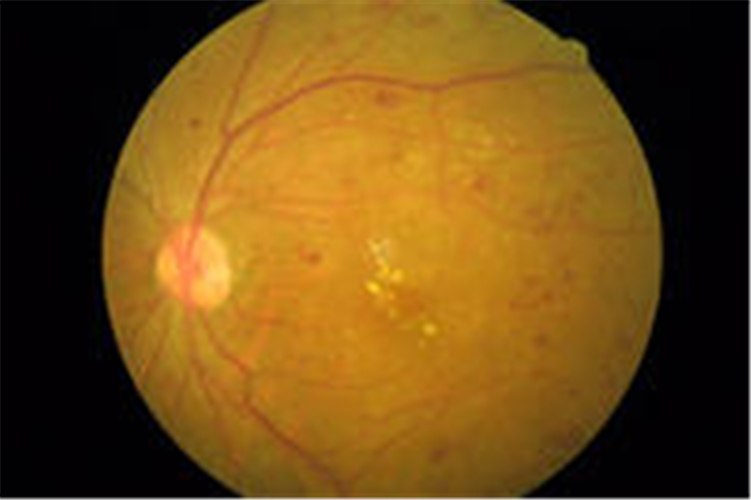

中心漿液性視網膜脫落

糖尿病人視網膜脫落